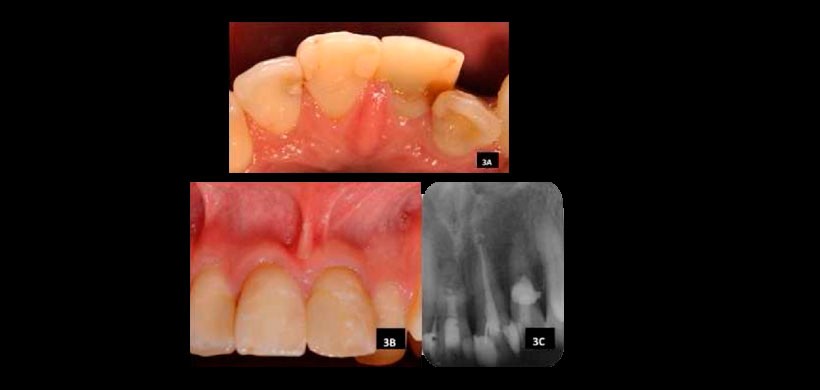

Figura 3: A) Vista palatina de los dientes 11 y 22; B) Vista bucal de la pieza 11 y 22; C) Radiografía periapical tres años después de la terminación del tratamiento